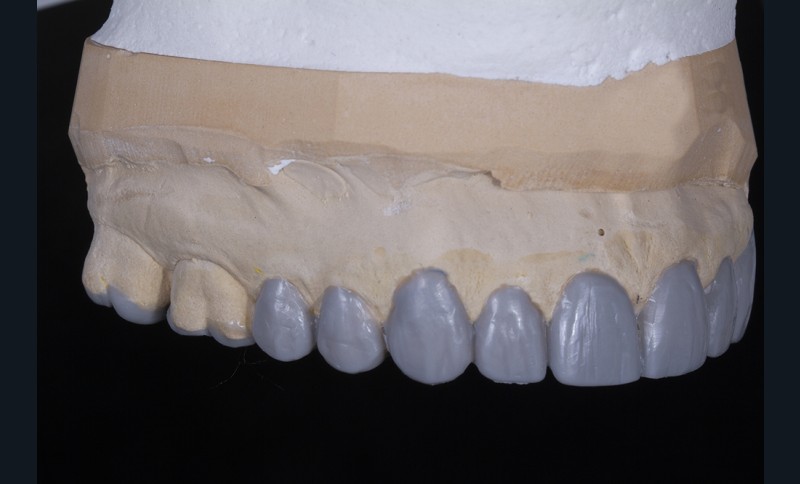

Dans un deuxième temps, un wax-up global permet de restaurer les courbes d’occlusion. Il est à noter que la présence d’égressions dentaires, faute d’antagoniste ou d’anciennes restaurations prothétiques inadaptées, crée des usures inégales au sein de la cavité buccale. Aussi, la présence de zones non recouvertes par le wax-up dans les secteurs postérieurs est courante, permettant ainsi la préservation de zones amélaires majeures pour le collage (fig. 2).